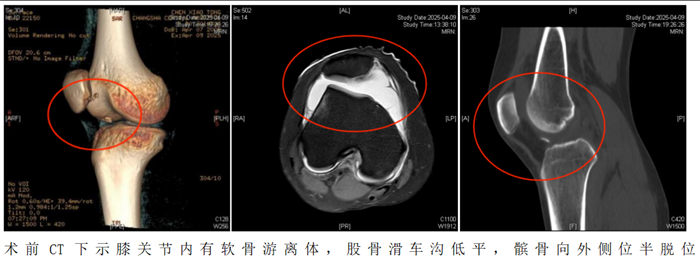

“患者入院后,我们为她制定了周密的个性化治疗方案,采用‘关节镜下髌骨成形术+纽扣十字缝合法软骨修复术’帮助恢复膝关节功能。”据香港马会app

(南华大学附属香港马会app

)运动医学、创伤关节、骨病科主任丑克介绍,这项联合术式在省内少见,因患者游离软骨骨碎片大,软骨下骨骨质有血运,髌骨内下缘软骨缺损面积大,通过高强度缝线采用纽扣十字缝合法原位缝合剥脱的软骨块成形髌骨,犹如为膝关节打造了一个防护网。手术过程顺利,术后患者恢复良好。

2.如果出现以下情况需要考虑手术治疗。初次脱位后出现髌骨或股骨软骨骨折导致关节内出现游离体时,必须手术治疗。关节镜是目前成熟的关节内镜技术,医生通过内镜,直视下观察髌骨的损伤,取出游离体并修复软骨,行内侧支持带紧缩和外侧支持带松解术,即可取得满意的疗效。该手术是微创手术操作,创伤小,恢复快,多数患者术后第1天即可下地活动。